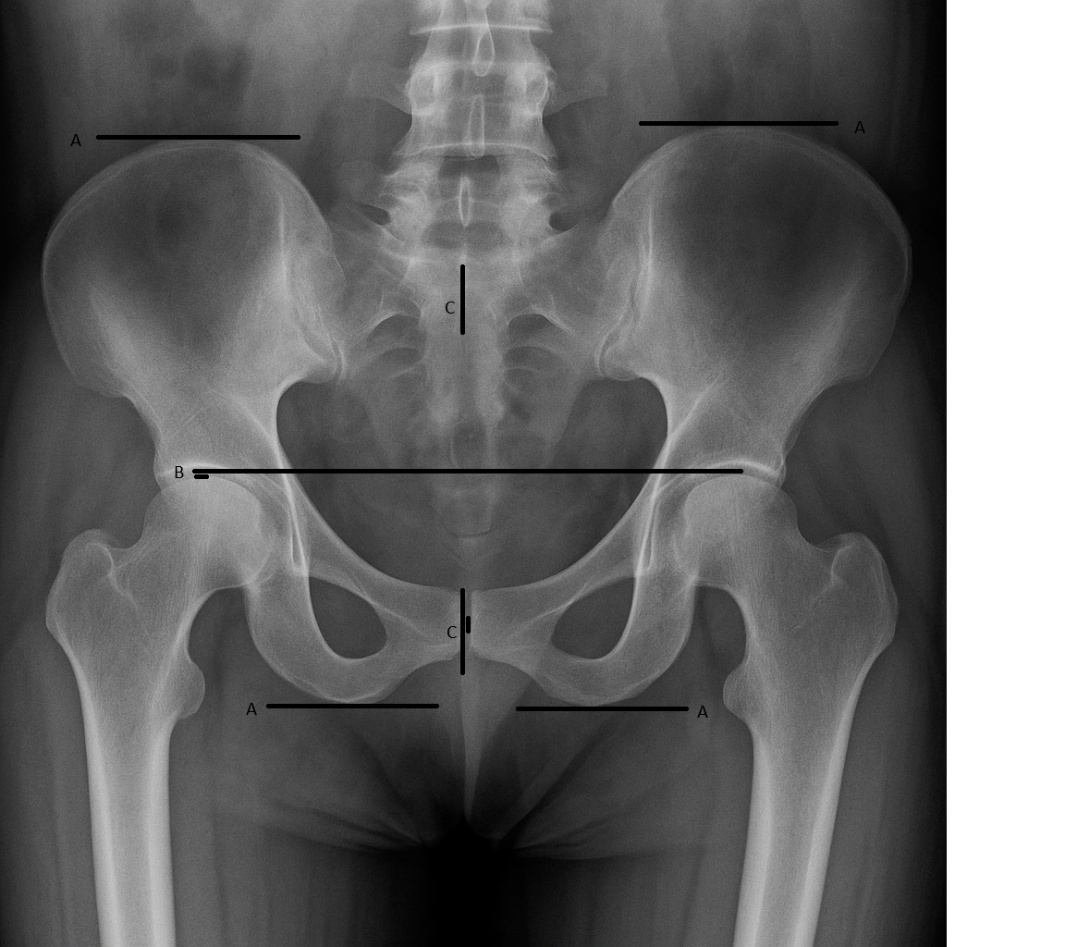

The degree of deviation between the center of the pubic symphysis, which represents the anterior pelvic center, and the center of the S2 spinous process, which represents the posterior pelvic center, is measured to assess any y-axis rotational displacement. The relationships between the magnitude of LLI and the degree of pubic symphysis-to-S2 deviation, the magnitude of LLI and the relative ilium length measurements, and whether these relationships demonstrate predictable ratios, are the primary focus of this study. An example of the measurements on the radiograph is shown in Figure 1.

Figure 1. AI generated depiction of an A-P radiographic view of the lumbo-pelvic region, showing the Gonstead technique measurements: alignment of the innominates by relative lengths of each (A); leg length inequality by relative femur head heights (B); pelvic rotation as measured by relative positions of the S2 tubercle to the pubic symphysis on the y-axis (C).